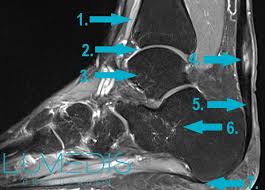

Schmerzen In Der Wade Lumedis Muskelspezialisten